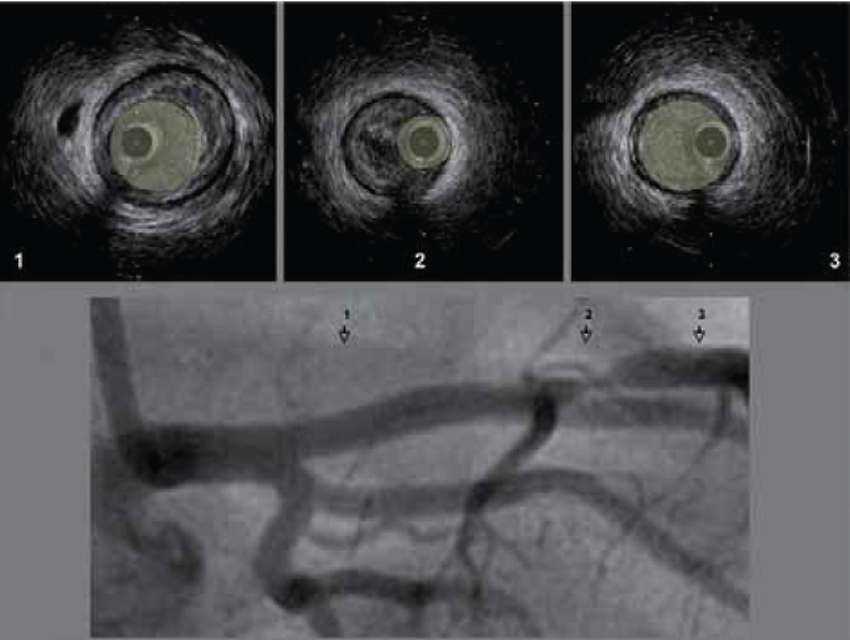

6 . 2 . 2  -  Échographie endocoronaire (figure 7)

Figure 7 : L’échographie endocoronaire révèle des lésions non décelées par la coronarographie

1. plaque vulnérable (coeur lipidique) ; 2. sténose athérothrombotique (instable) ; 3. artère normale (lumière/ intima-média).

Cet examen n’est pas de pratique courante. C’est un procédé invasif qui permet l’analyse de la paroi coronaire (pariétographie).

Après réalisation d’une coronarographie, une sonde ultrasonique est introduite dans une artère. Le retrait automatique du capteur permet le recueil d’images en coupe du vaisseau qu’il est ensuite possible de reconstruire par des procédés informatiques en trois dimensions.

Elle permet de caractériser les lésions (inflammatoires ou lipidiques hypoéchogènes, fibreuses ou calcifiées hyperéchogènes, cellulaires intermédiaires) et de mesurer la surface artérielle au niveau des zones pathologiques.